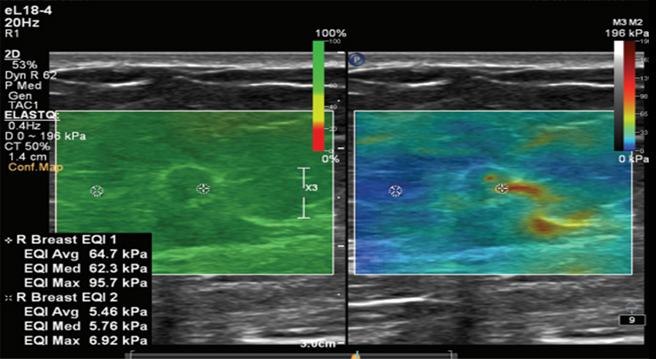

유방탄성초음파는 유방 혹의 탄성(단단하거나 부드러운 정도)을 측정하는 방법입니다.

혹을 손으로 만져보지 않아도 탄성초음파를 통해 정확하고 객관적인 진단이 가능하며,

전단파 탄성초음파는 초음파 검사 시 혹에서 발생한 전단파를 색으로 나타내는 기법입니다.

유방 탄성초음파의 경우, 초음파 검사에서 유방 혹이 악성일 가능성이 있을 경우에 보다 정확하고 객관적인 감별을 위해 사용됩니다.

유방암 혹은 악성가능성이 높은 혹은 비교적 단단한 형질을 띄므로 붉은 색에 가까운 색상을 띄게되고, 양성 병변의 경우 푸른 색을 띄게 됨으로써 시각적으로 명확하게 구분할 수 있습니다.

유사랑영상의학과에서는 필립스 EPIQ Elite 모델을 사용하고 있으며, 대학병원급의 프리미엄 사양입니다. 빠른 검사속도와 기존 초음파보다 더욱 뛰어난 화질의 장점을 가지고 있어 작은 유방암도 오차없이 정확한 판독이 가능합니다. 신의료기술 인정을 받은 검사로, 비급여 의료기술입니다.